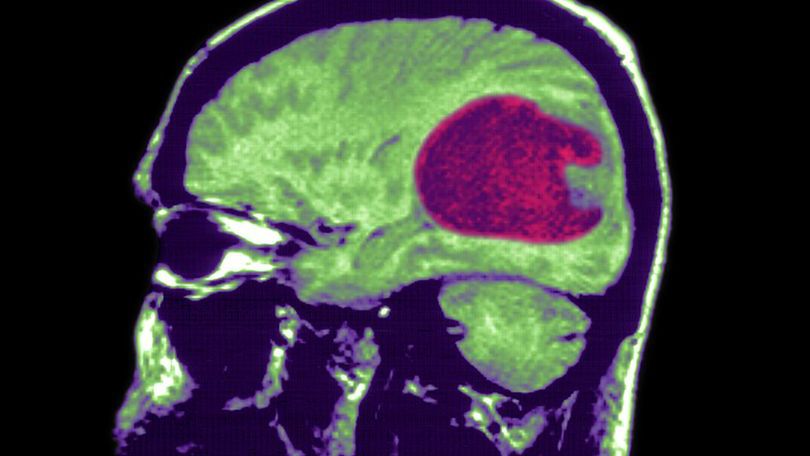

W opublikowanych w środę badaniach Journal of Environmental and Public Health przedstawiono wzrost liczby złośliwych guzów mózgu w latach 1995-2015 w Anglii. Według badań, liczba wzrosła dwukrotnie z 2,4 do 5 chorych na 100 tys. osób.

Nie ma pewności, czy telefony mogą powodować raka mózgu, jednak według Alasdaira Philipsa, głównego autora badań, wydaje się to najbardziej prawdopodobne. Guzy znajdują się przede wszystkim w okolicy płatów czołowych i skroniowych, czyli w okolicach uszu oraz oczu. To zwiększa jeszcze podejrzenie. Autor badania sugeruje, aby nie panikować. Jednak mówi, że warto dmuchać na zimne i przypadku prowadzenia długiej rozmowy korzystać ze słuchawek.